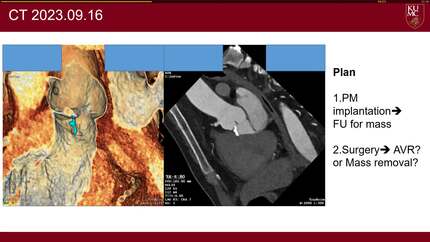

A case of severe aortic regurgitation due to rupture of an aortic strand